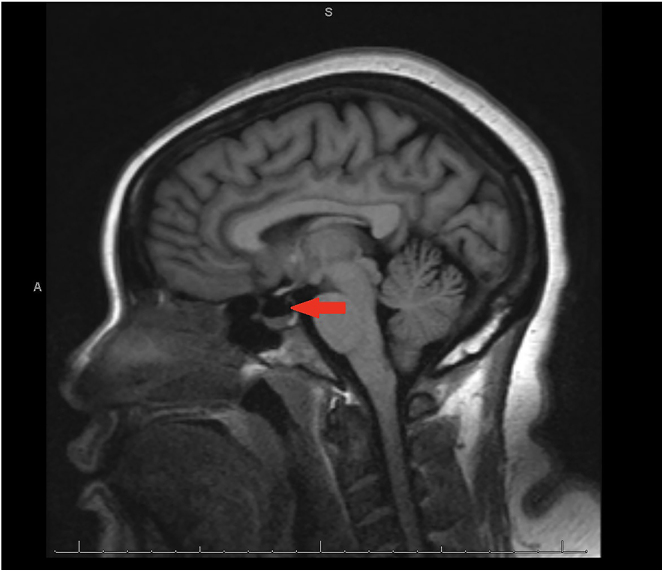

We report a case of a 43-year-old woman with stage IIB triple-negative breast cancer (TNBC) on neoadjuvant pembrolizumab presenting in adrenal crisis. Biochemical evaluation revealed isolated adrenocorticotropic hormone (ACTH) deficiency, and MRI demonstrated a partial empty sella; findings consistent with pembrolizumab-induced hypophysitis. Glucocorticoid replacement therapy led to symptom resolution. Pembrolizumab-induced hypophysitis is rare (incidence ∼0.98%), often associated with isolated ACTH deficiency, making diagnosis challenging due to nonspecific symptoms and frequently unremarkable pituitary imaging. As ICI use expands, clinician awareness of immune-related adverse effects (irAEs) is essential to prevent life-threatening complications and improve outcomes.

我们报告一例43岁女性IIB期三阴性乳腺癌(TNBC)新辅助派姆单抗呈现肾上腺危机。生化评估显示孤立的促肾上腺皮质激素(ACTH)缺乏,MRI显示部分空鞍;结果与派姆单抗诱导的垂体炎一致。糖皮质激素替代治疗导致症状缓解。pembrolizumab引起的垂体炎是罕见的(发生率约0.98%),通常与孤立的ACTH缺乏相关,由于非特异性症状和经常不显著的垂体成像,使得诊断具有挑战性。随着ICI使用的扩大,临床医生对免疫相关不良反应(irAEs)的认识对于预防危及生命的并发症和改善预后至关重要。